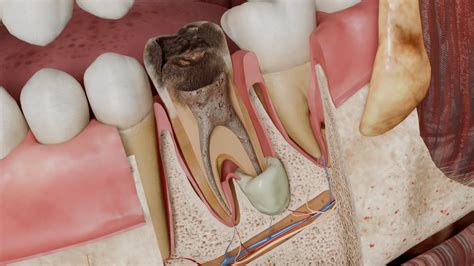

El diagnóstico de la periodontitis apical aguda supurativa se basa en la evaluación clínica y radiográfica. Los síntomas clínicos pueden incluir dolor intenso, sensibilidad a la percusión, inflamación y presencia de un absceso con drenaje purulento. Radiográficamente, se puede observar una lesión radiolúcida periapical, aunque en las etapas iniciales de la infección, los cambios radiográficos pueden ser sutiles o incluso ausentes.

- Drenaje del Absceso: El drenaje del absceso es esencial para aliviar la presión y eliminar el exudado purulento. Esto se puede lograr mediante la apertura del conducto radicular o mediante una incisión en la mucosa para drenar el absceso a través de los tejidos blandos.

- Desinfección del Conducto Radicular: La desinfección del conducto radicular es fundamental para eliminar las bacterias y los productos tóxicos que causan la infección. Esto se realiza mediante la instrumentación mecánica del conducto, seguida de la irrigación con soluciones antimicrobianas como el hipoclorito de sodio (NaOCl).

- Medicamentos Intracanal: Después de la desinfección, se puede colocar un medicamento intraconducto, como el hidróxido de calcio (Ca(OH)2), para mantener el control de la infección y promover la curación. El hidróxido de calcio tiene propiedades antimicrobianas y antiinflamatorias, y ayuda a crear un ambiente desfavorable para el crecimiento bacteriano.

- Obturación del Conducto Radicular: Una vez que la infección está controlada y los síntomas han disminuido, se procede a la obturación del conducto radicular con un material biocompatible, como la gutapercha, para sellar el conducto y prevenir la reinfección.

- Absceso Periapical Agudo: Después de la segunda cita, la paciente desarrolló un absceso periapical agudo con comunicación a la cavidad oral. Se realizó el drenaje intraconducto e intralesional del exudado purulento.

- Extrusión de Hidróxido de Calcio: Durante la aplicación de hidróxido de calcio, se produjo una extrusión accidental hacia los tejidos periapicales.

- Curación y Sellado Apical: En citas posteriores, se verificó la curación favorable de los tejidos blandos, se limpió el conducto, se aplicó hidróxido de calcio y se selló temporalmente la cavidad de acceso. Una vez desaparecieron los síntomas y el exudado, se realizó el sellado apical con un tapón de 5 mm de EVO MTA, seguido del sellado del resto del conducto con adhesivo, X-tra base y composite.